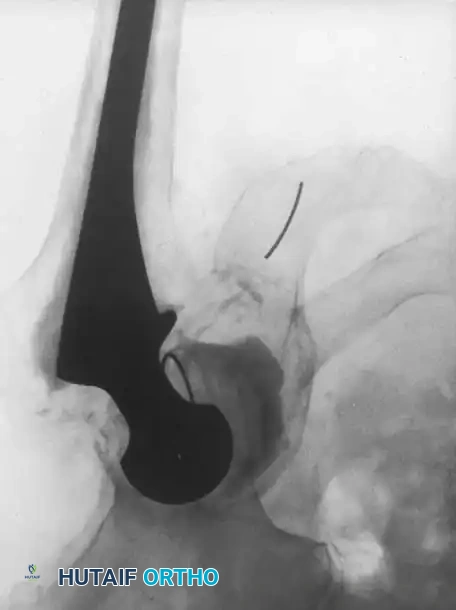

Associated Surgical & Radiographic Imaging